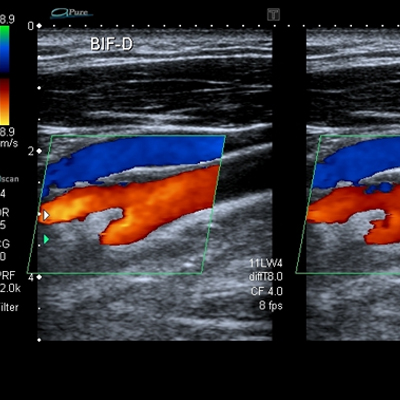

Ultrasonido Doppler carotídeo

El ultrasonido carotídeo, mediante ondas de ultrasonido genera imágenes de los vasos encargados de la irrigación cerebral y permite la detección de sitios de obstrucción o alteraciones del flujo.

Ultrasonido vascular periférico

Es un estudio no invasivo, que utiliza ondas sonoras para evaluar el sistema circulatorio del cuerpo, y permite identificar alteraciones del flujo en venas y arterias, así como sitios de obstrucción.